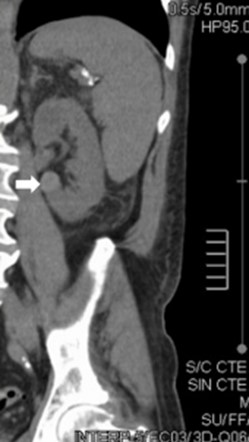

La Categoría IIF exhibe múltiples septos finos en su interior, realce evidente en paredes o septos, mínimo grado de engrosamiento de la pared, calcificación grosera o nodular, lesiones intra renales densas sin realce o con realce de septos o pared, siendo este realce no medible en las lesiones descubiertas con incremento de la densidad radiológica cuando se comparan las imágenes sin y con contraste yodado IV. Se consideran masas quísticas moderadamente complicadas y precisan seguimiento con controles cada seis meses.(19, 20) No requieren tratamiento quirúrgico inmediato y el riesgo de evolucionar a quistes malignos es del 5%, quistes con aspecto hiperdenso > 3 cm (Anexos 7 y 8).

La Categoría III muestra engrosamientos lisos o irregulares de la pared o de los septos intra quísticos y existencia de realce medible en TC y RMI. Se consideran masas indeterminadas y precisan de primera instancia cirugía, nefrectomía parcial o ablación por radiofrecuencia, salvo contraindicaciones clínicas.(19, 21) Aproximadamente el 40%-60% son lesiones malignas (carcinomas renal quístico), siendo el restante benignas, que incluyen quistes hemorrágicos, infectados crónicos o calcificaciones parietales, nefrona quístico multiloculado, quistes multilobulados, quistes con tabiques complejos, etc. (Anexos 9 y 10).